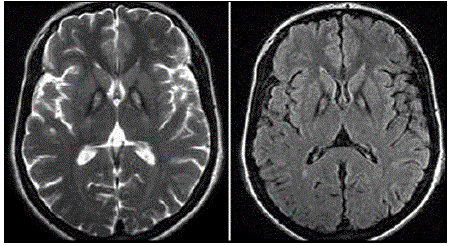

Paciente, sexo masculino, 29 anos de idade, apresenta quadro de parkinsonismo (ridigez em roda denteada e bradicinesia principalmente); distonia cervical; disartria e disfonia discretas; alteração comportamental com surtos psicóticos; retinopatia pigmentar; e, sinais de liberação piramidal ao exame físico neurológico. O quadro tem apresentado piora progressiva ao longo do tempo. Foi realizada a seguinte Ressonância de Crânio (RM de crânio); observe:

Assinale o provável diagnóstico desse paciente.